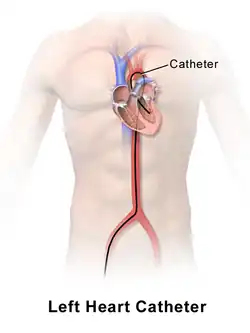

Left heart catheterization (LHC)

Left heart catheterization (LHC) is an ambiguous term and sometime clarification is required:

- LHC can mean measuring the pressures of the left side of the heart.

- LHC can be synonymous with coronary angiography.

technique is also used to assess the amount of occlusion (or blockage) in a coronary artery, often described as a percentage of occlusion. A thin, flexible wire is inserted into either the femoral artery or the radial artery and threaded toward the heart until it is in the ascending aorta. Radial access is not associated with an increased risk of stroke over femoral access.[5] At this point, a catheter is guided over the wire into the ascending aorta, where it can be maneuvered into the coronary arteries through the coronary ostia.[4] In this position, the interventional cardiologist can inject contrast and visualize the flow through the vessel. If necessary, the physician can utilize percutaneous coronary intervention techniques, including the use of a stent (either bare-metal or drug-eluting) to open the blocked vessel and restore appropriate blood flow. In general, occlusions greater than 70% of the width of the vessel lumen are thought to require intervention. However, in cases where multiple vessels are blocked (so-called "three-vessel disease"), the interventional cardiologist may opt instead to refer the patient to a cardiothoracic surgeon for coronary artery bypass graft (CABG; see Coronary artery bypass surgery) surgery.